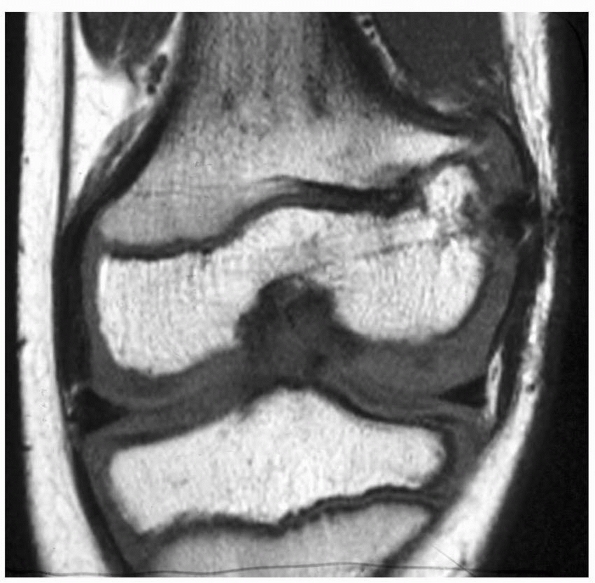

a skeletally immature child, further evaluation often is warranted. CT

scanning with sagittal and coronal reconstructions (orthogonal to the

area of interest) may demonstrate clearly an area of bone bridging the

physis between the epiphysis and metaphysis (see Fig. 5-32C,D). MRI is also a sensitive method of assessing normal physeal architecture (Fig. 5-34).34,48,56

| Figure 5-34 MRI scan of a patient with traumatic lateral distal femoral partial growth arrest. Note Harris arrest line tapering to the site of the arrest. |